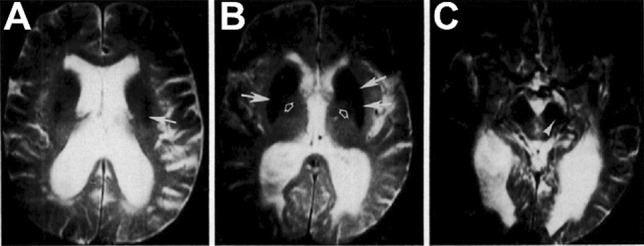

Fig. 5

Early T2-weighted magnetic resonance imaging using a 1.5 T field strength of iron in a multiple system atrophy. White arrows in ab denote decreased signal intensity, indicating iron deposits, in the putamen and caudate nucleus compared to the globus pallidus (open arrows, (b)). Hypointensity marked with the white arrowhead (c) was interpreted as indicative of specific iron accumulation in the substantia nigra pars compacta. Reproduced from Drayer et al. 1986a with permission from the

Radiological Society of North America (copyright 1986)

Interest in the role of iron in the pathophysiology of parkinsonism was boosted by recognition of the ability of magnetic resonance imaging (MRI), developed during the 1970s and introduced into the clinic in the 1980s, to detect and quantitate iron in the brains of living patients, particularly the substantia nigra. The paramagnetic properties of brain non-heme iron cause local areas of magnetic field inhomogeneity that reduce transverse relaxation times (T2) (Drayer et al. 1986b). In early studies, however, MRI findings were only incompletely correlated with post mortem reports based on Perls staining for iron. Initial imaging studies of living patients, some investigators found that nigral iron levels were reduced in parkinsonism (Rutledge et al. 1987), while others found iron deposits in the putamen, caudate, and substantia nigra compacta (Fig. 5) in patients with multisystem atrophy or progressive supranuclear palsy (Drayer et al. 1986b). Subsequent studies with larger numbers of patients (Antonini et al. 1993) and stronger magnetic fields (Gorell et al. 1995) confirmed that areas of T2-weighted hypointensity were typical in the nigra, caudate, and putamen in parkinsonism, but "shortening of T2 values in the substantia nigra did not correlate with disease duration nor with clinical severity" (Antonini et al. 1993). That is, nigral iron deposits were an early feature of parkinsonism, consistent with their playing a causative role in its pathogenesis, but also with their being unrelated to the disease process altogether.